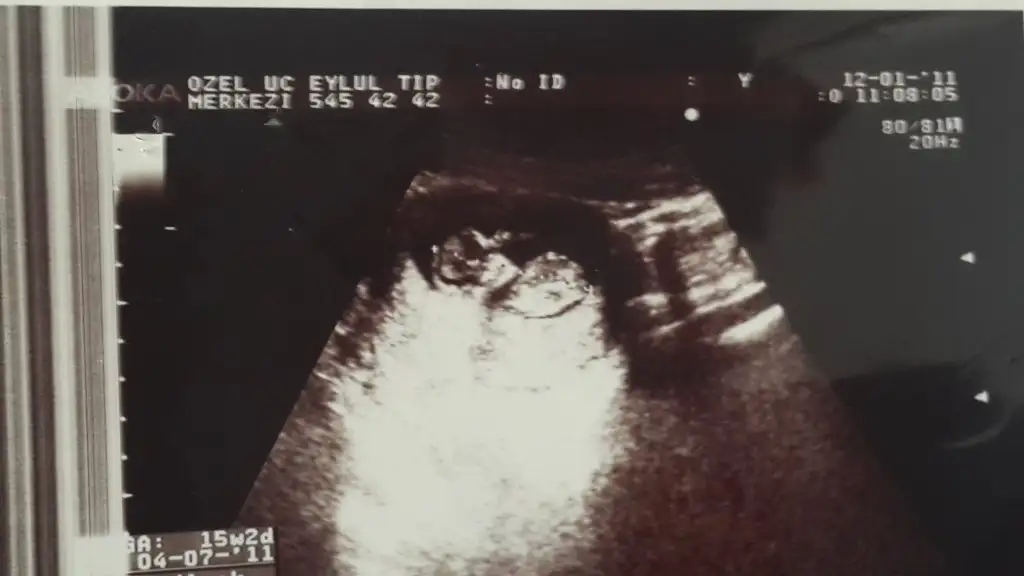

Biraz önceki yan yüklendi şimdi düz olanını yukluyorym

Eklentiler

• 20150903_173152.webp

20150903_173152.webp

16,8 KB · Görüntüleme: 91